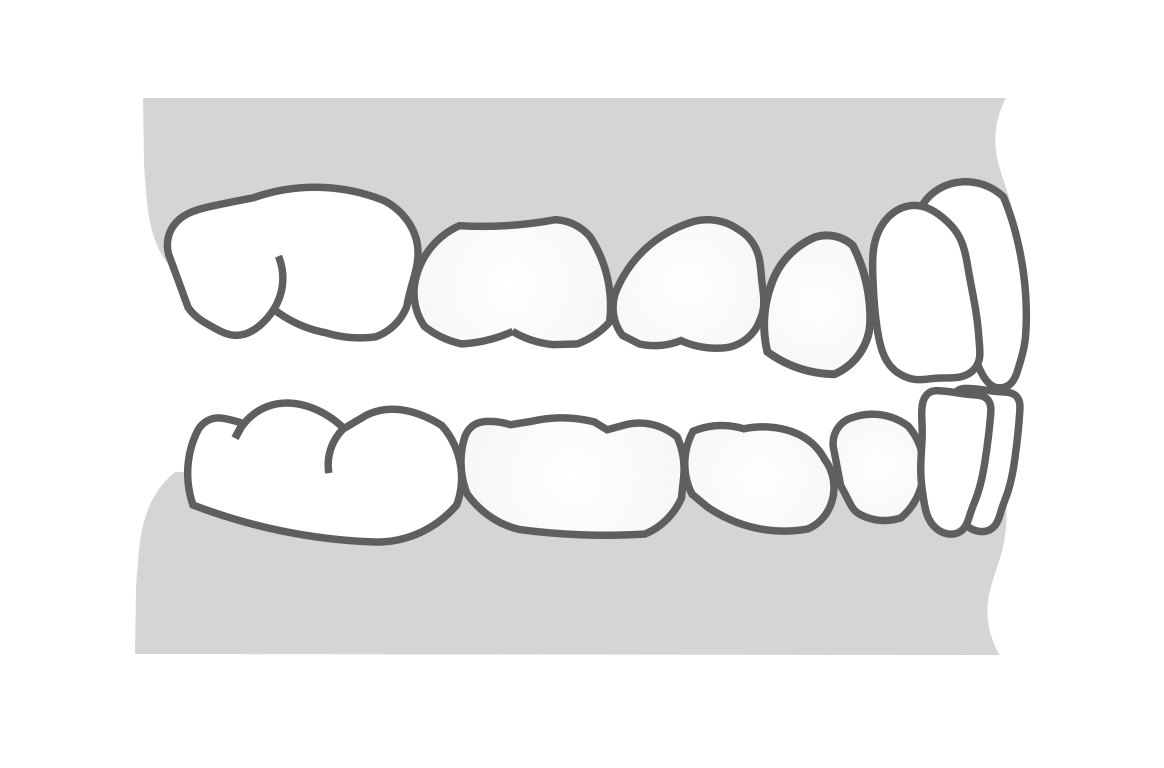

下あごの左右差

下あごの長さに左右差がある場合は、思春期の成長期に悪化する可能性があり1期治療後に注意が必要となります。「上の歯並びの正中から下の歯並びから3mm以上ずれている」、「奥歯の噛み合わせに左右差がある」、「片方だけ奥歯がクロスバイトにかみ合っている」などの場合は、1期矯正で一時的に治療が成功しても、成長期に再悪化する可能性が高くなります。

上下の正中線がずれていても前述の早期接触が原因のケースもあるため、よく見分ける必要があります。早期接触が原因で下あごが左右にずれる場合は、引っかかっている下の前歯に歯肉退縮がみられることが多いです。